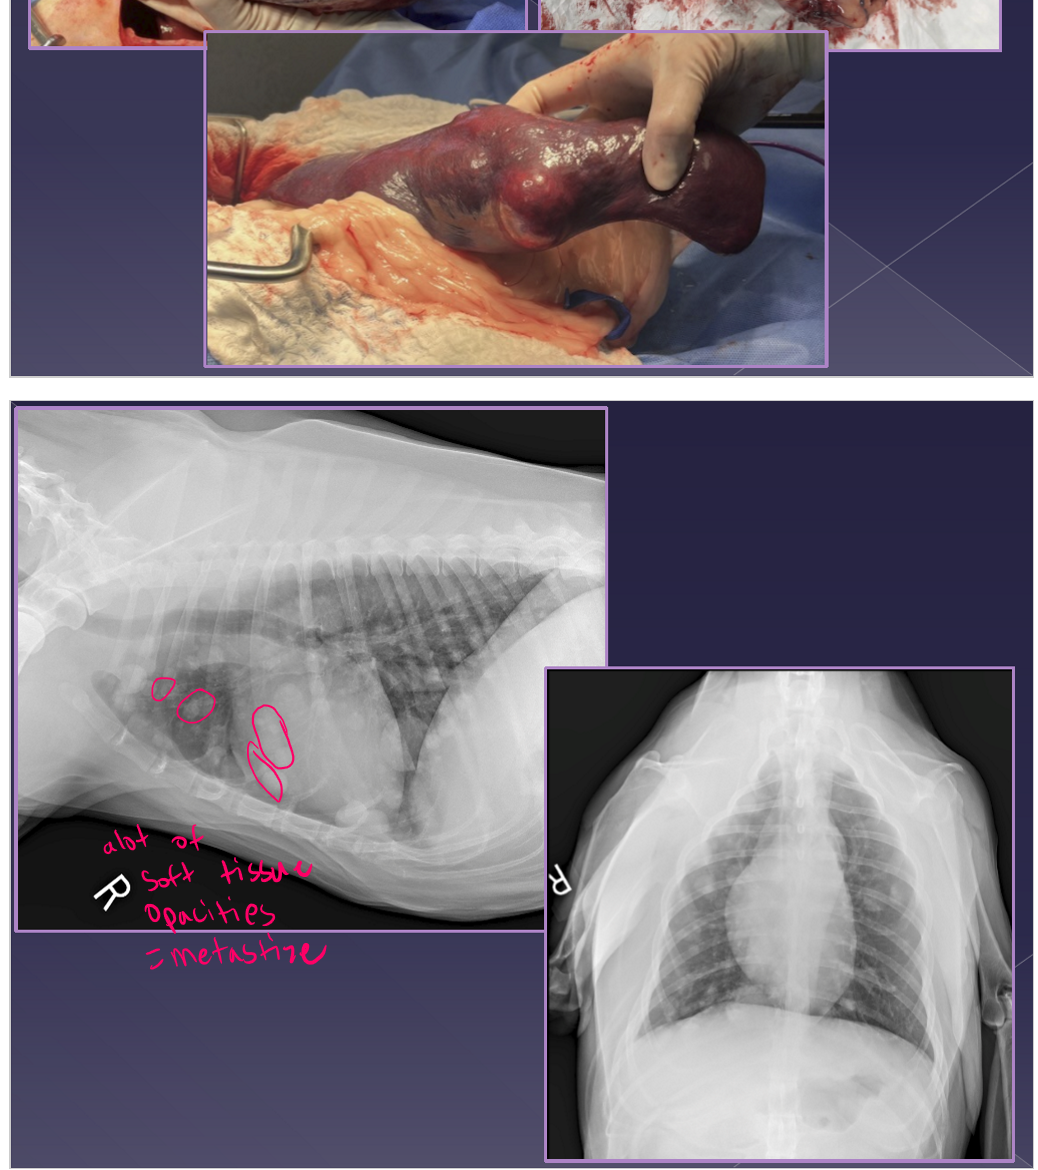

Neoplasia of the spleen

benign or malignant

very common

large breed dogs » small breed dogs

acute

shock, enlarged abdomen, abdominal mass, fluid wave, lethargic, vomiting, abdominal pain

chronic

same as acute but episodic presentation

diagnosis

abdominal radiographs

mass-effect

peritoneal effusion

thoracic radiographs

metastasis

ultrasound

mixed echotexture

cavitated lesions

enlarged spleen

spleen neoplasia

differentials

non-neoplastic

hematoma

benign neoplasia

Lipoma / myelolipoma

hemangioma

fibroma

malignant neoplasia

Hemangiosarcoma* - most common

fibrosarcoma

liposarcoma

mast cell tumor

treatment

cardiovascular stabilization

electrocardiogram

± blood transfusion

splenectomy